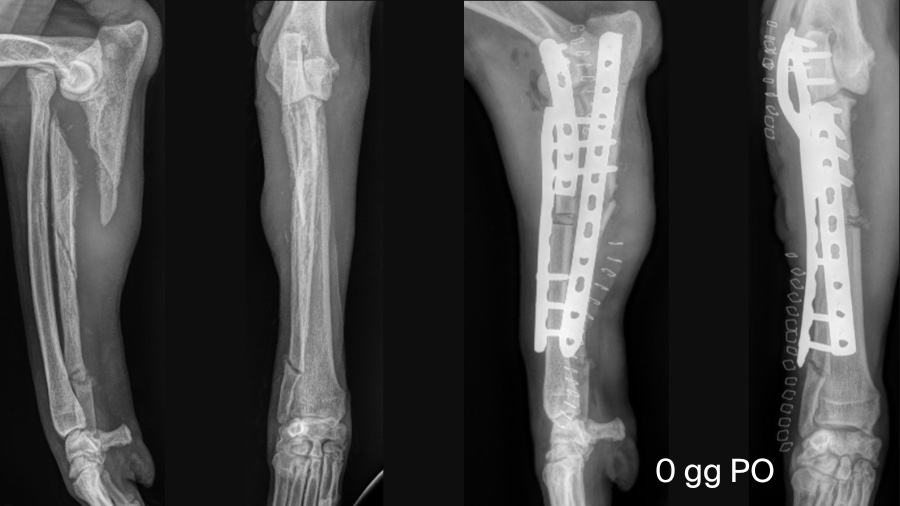

Accurate and timely diagnosis is the foundation for successful treatment. Dogs with chronic Monteggia fractures often present with severe, non-weightbearing lameness, marked pain upon elbow manipulation, and a restricted range of motion. In chronic cases, like the 12-year-old Giant Schnauzer referenced here, these signs may persist or worsen weeks after the initial injury, especially if the trauma was not recognized or properly managed (as with bite wounds).

Orthogonal and comparative radiographs are essential. Look for an ulnar diaphyseal fracture and displacement of the radial head, typically cranially or laterally. It’s easy to miss the luxation if you focus solely on the ulna, so a careful evaluation of elbow congruence is critical. Advanced chronicity leads to periarticular fibrosis and remodeling, which complicates both diagnosis and treatment. Awareness of this injury pattern can prompt early referral and improve prognosis.

Managing chronic Monteggia fractures demands surgical flexibility. In chronic cases, anatomical reduction of the radial head is often blocked by fibrosis and altered bone surfaces. In our case, open reduction alone was insufficient, so a radial ostectomy was performed to shorten the radius and facilitate reduction.

Stabilization of the ulnar fracture was achieved with a locking compression plate (LCP), while the radial ostectomy was fixed with a cranial LCP. Intraoperative challenges are not uncommon—here, an iatrogenic rupture of the lateral collateral ligament required immediate attention. We restored elbow stability using two suture anchors (one on the humeral condyle and one on the radial head) connected with absorbable suture material. A contoured locking plate was also used for temporary trans-articular stabilization of the elbow.